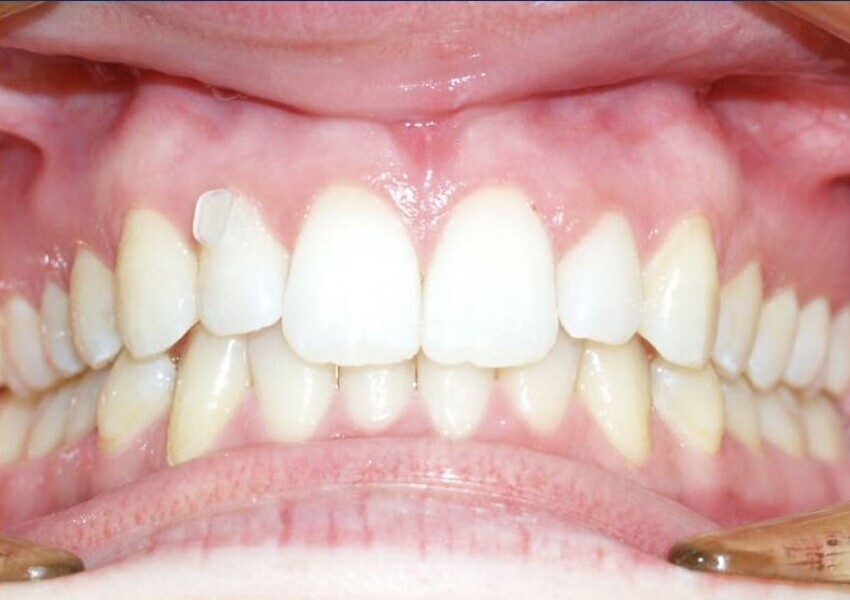

Extrusions

Aligners alone will fail because of the push that clear aligners produce, being very difficult to translate into the pull required to extrude teeth. Again, this is so despite brilliant attachments that incorporate inclined planes in attempts to overcome this limitation. Instead use fixed devices that will much more assuredly deliver extrusion. These can include buttons or elastics, intra- or inter-arch, or even fixed appliances first, transitioning to aligners alone once the extrusions have been produced (Figs. 4–9). The outcome is the delivery of true extrusion in a timely and effective manner early on and with less chance of aligner tracking loss.

Fig. 9: After three months of extrusion.